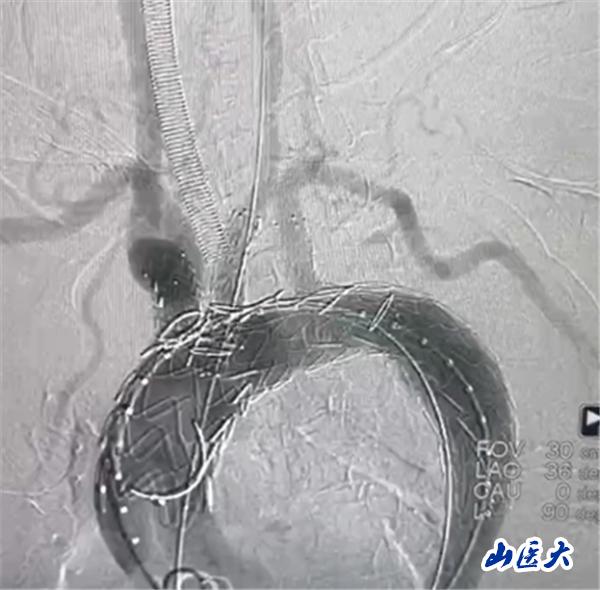

术中造影结果

术后效果

首例患者是一位55岁的女性,她患有高血压约2年时间,平时也会规律服用多种降压药,但血压控制始终不尽人意。2023年4月下午,她出现不明原因的头痛,在家拔罐缓解少许便未到医院就医,次日凌晨突感胸闷、胸背疼痛伴有呼吸困难等症状、家人急忙拨打了120,把患者送入医院急诊科进行救治,医生在急诊科行胸腹主动脉CTA时,显示主动脉弓部-降主动脉及腹主动脉壁间血肿,遂收治入医院血管外科,患者入院10天后复查血肿仍未有改善,依然伴有胸背部疼痛等不适,如不进一步处理,可能发展为夹层危及生命,患者及家属经过与医生团队了解沟通,决定进行创伤小、恢复快的介入手术治疗。张玮教授、符伟国教授、董红霖教授及其血管外科团队(闫盛、常文凯、田琴琴)共同商讨手术方案,最终确定使用Zipper™一体式主动脉弓覆膜支架系统,行胸主动脉覆膜支架腔内隔绝术+无名动脉、左颈总动脉、左锁骨下动脉分支重建术为患者进行治疗。董红霖教授及其血管外科团队根据患者术前头颅CT平扫提示双侧侧脑室旁缺血灶,血压控制不稳定,属夹层壁间血肿非典型夹层等风险点,制定了完整的手术方案,术中经股动脉置入Zipper支架主体,经预留导丝超选无名动脉,并确保主体支架对位准确,顺利置入左颈总动脉、左锁骨下动脉支架,重建弓上三分支。手术过程非常顺利。术后观察主动脉及分支覆膜支架定位准确;无内漏;分支支架通畅,动脉供血正常。